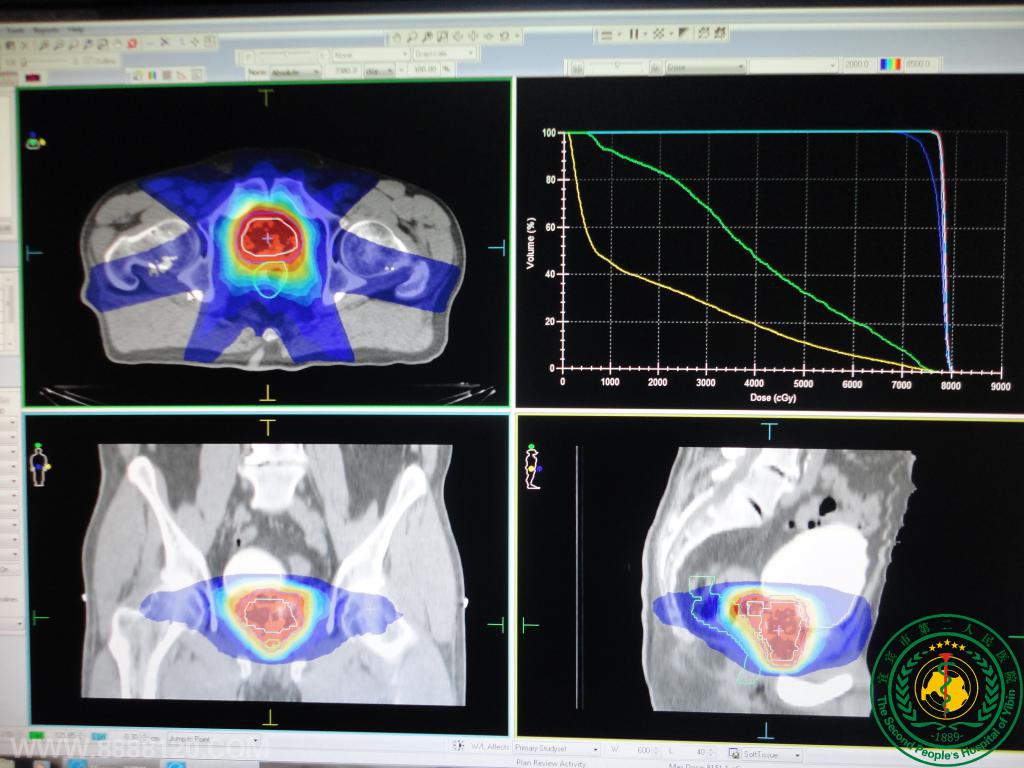

盆腔肿瘤及肺癌3DCRT靶区、射野及DVH放疗科特色技术放疗科特色技术放疗科特色技术放疗科特色技术